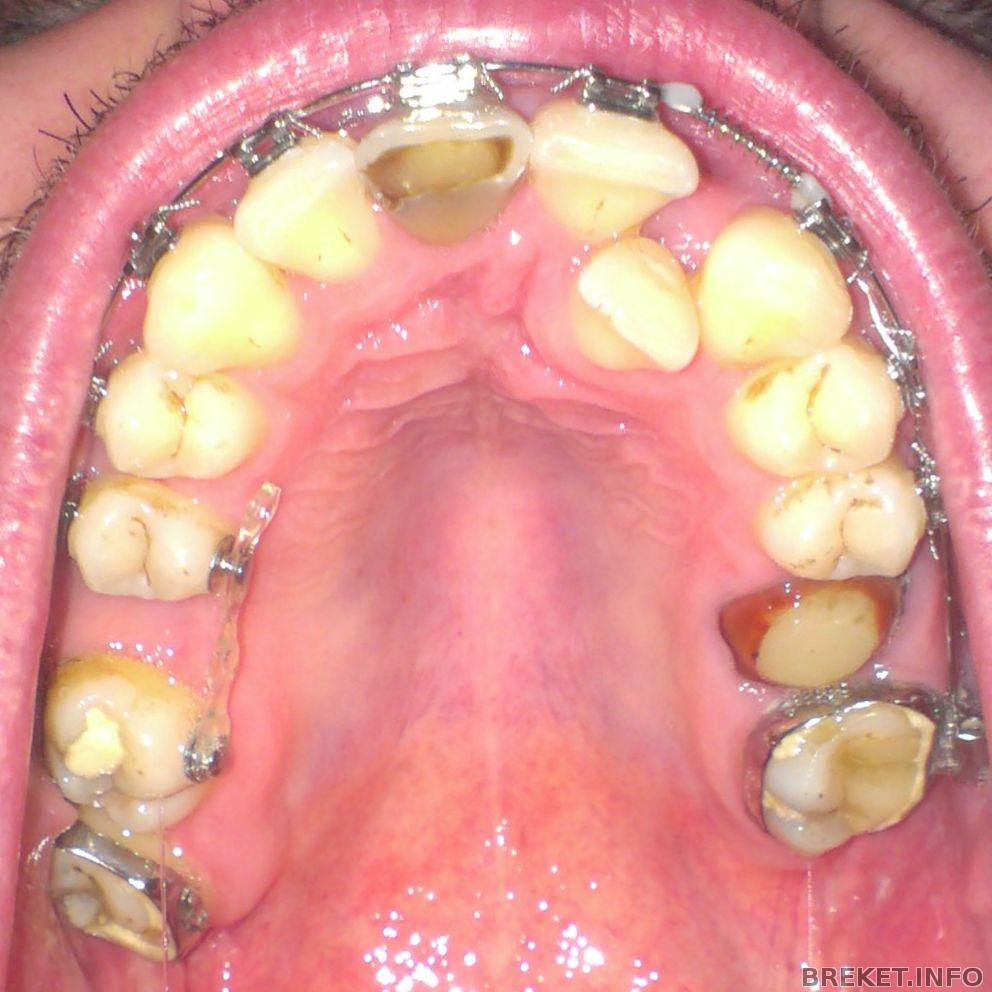

Кстати сегодня был у своей ортофеи на приеме, поменяла она мне проволоку на лигатурные тяги) Поставила как с внешней стороны, так и с внутренней) Днем зуб болел, сейчас чучуть только, когда сильно давишь на зуб... Но хочу сказать что за сегодня моя пятерочка сдвинулась уже на пол 0,5мм наверное) И промежуток единички и троечки еще больше стал!) Не на много, но прогресс есть) Следующий прием 4 февраля, будем дугу менять! Только незнаю на какую...

Хочу сделать чистку зубов, т.к. есть налет небольшой, на фото даже видно, и врач сказал что на ВЧ желательно все фиссуры почистить, и сделать менее выраженными, т.е. не такими глубокими, заполнив их пломбами.. Чтоб они лучше при чистке зубов прочищались) Думаю не плохая идея) Но из-за кнопочек пока нельзя делать чистку, так что как только, так сразу.

В день установки тяги 23.01.14 (вечером).